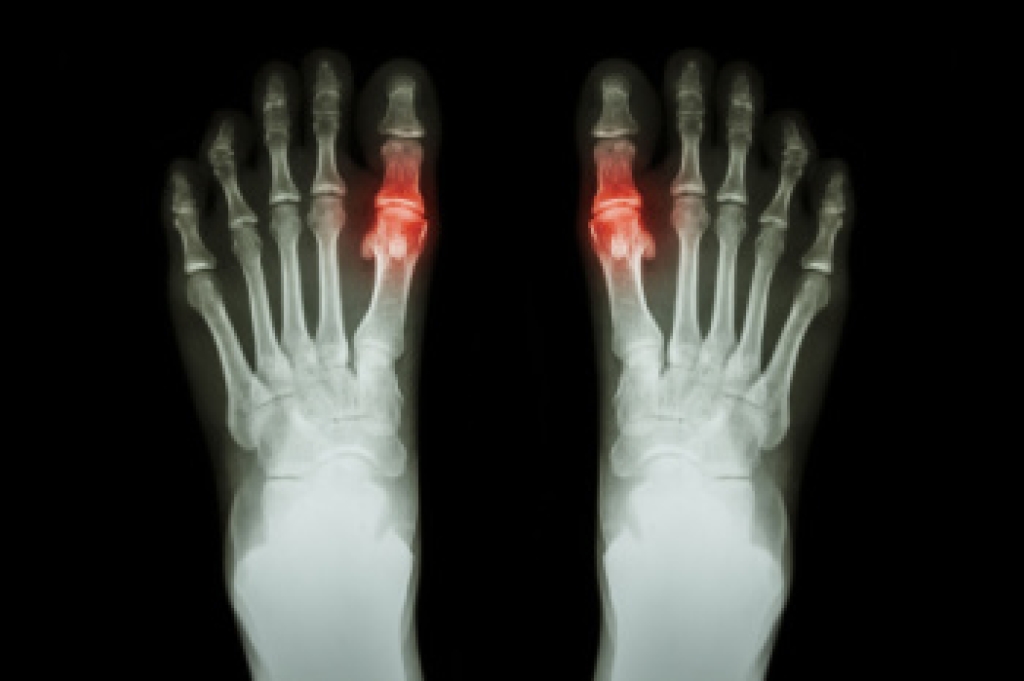

Understanding Chronic Tophaceous Gout

Chronic tophaceous gout is an advanced form of gout that develops when uric acid builds up in the body. The result is hard deposits, called tophi, that form around joints and soft tissues. Uric acid is a natural waste product, but high levels can lead to crystal formation that triggers inflammation, causing swelling, warmth, and severe pain. Over time, these deposits may grow and cause joint damage, stiffness, and reduced movement. They can also press on nearby nerves and affect walking. A podiatrist can diagnose chronic tophaceous gout through imaging or fluid testing, which identifies uric acid crystals. Treatment options include medication to lower uric acid levels and reduce inflammation, as well as care to protect the joints and prevent further damage. In severe cases, surgery may be needed to remove large tophi. If you are experiencing severe pain from gout, it is suggested that you make an appointment with a podiatrist for treatment.

Gout is a type of arthritis caused by a buildup of uric acid in the bloodstream. It often develops in the foot, especially the big toe area, although it can manifest in other parts of the body as well. Gout can make walking and standing very painful and is especially common in diabetics and the obese.

Gout can easily be identified by redness and inflammation of the big toe and the surrounding areas of the foot. Other symptoms include extreme fatigue, joint pain, and running high fevers. Sometimes corticosteroid drugs can be prescribed to treat gout, but the best way to combat this disease is to get more exercise and eat a better diet.